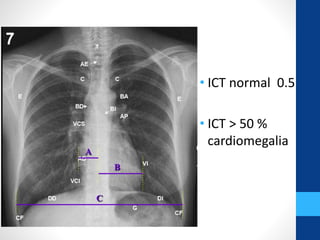

Índice Cardiotorácico | Alejandra Sernaque Herrera | uDocz

Índice Cardiotorácico | Estudiante de radiología, Estudiante de ...

Como medir el índice cardiotorácico (ICT) en la radiografía PA de tórax ...

Índice cardiotorácico (ICT | PDF | Corazón | Medicina Interna

Grados-de-Cardiomegalia-de-Acuerdo-al-ICT.pptx

Índice Cardiotorácico (ICT) - YouTube

Índice cardiotorácico | MARIA SEGURA | uDocz

INDICE cardiotorácico (Cardiomegalia) - YouTube

Índice cardiotorácico - Método y valores normales Sobre la placa ...